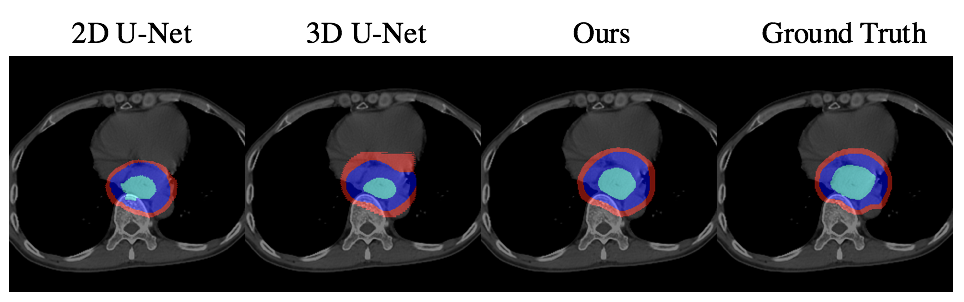

To evaluate our method, we chose the most commonly used CNN-based segmentation frameworks: 2D U-Net[8] and 3D U-Net[4] as our baselines. Since we focus on predicting the accurate radiotherapy target contouring, we trained and tested with valid slices that contain tumors. That is, given the volume where oncologists want to deliver radiation, we are able to segment the GTV, CTV and PTV regions precisely. For quantitative comparison, following metrics in [5], we use DSC, Sensitivity, and Specificity and ran with five-fold cross-validation. Table. 1 and Figure. 2 shows that our non-interactive method outperforms all the baselines both qualitatively and quantitatively. In the interactive setting, the results are evaluated on the selected sequences with “min median DSC” of GTV for each patient, in the exclusion of the slice we have reconstructed the features. As shown in Table. 2, the results are further improved after the interaction.